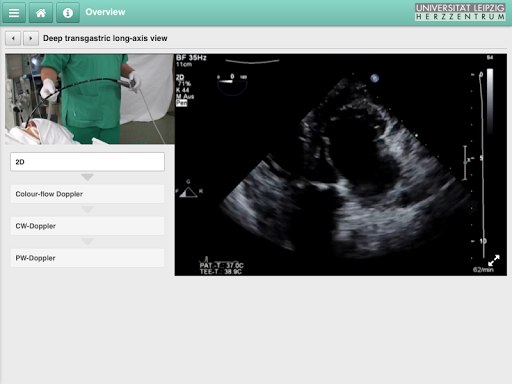

TEE as an APP. Transesophageal echocardiography (TEE) is an important diagnostic and monitoring modality of the cardiovascular system. To accurately depict a three dimensional structure with a two dimensional modality requires a structured and comprehensive approach to TEE.

The praxis trainer guides the novice echocardiographer through an easily reproducible step-by-step approach with flow diagrams and video loops to achieve a complete and comprehensive exam.

- Clear flow diagrams depict a useful sequence for the echocardiography examination

- Step-by step guide to transitioning from one view to another with the help of numerous annotated video loops

- Simultaneous illustration of manipulation of the TEE probe and image achieved on ultrasound

- Numerous still frames and video loops of the standard echocardiography views

- Explanation of essential probe settings, measurements and analysis of these values

- Examples of normal physiology as well as important pathological findings on echocardiography